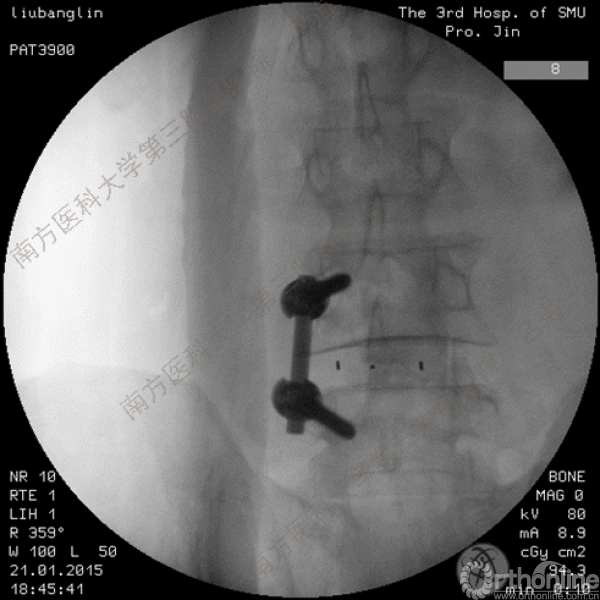

随着社会老龄化进程加快,胸腰椎退行性病变的治疗已经成为脊柱学术界的一个热点话题。MIS-TLIF手术可以治疗多种不同的胸腰椎退行性疾病,南方医科大学第三附属医院吕海教授结合病例为我们一一展示了该术式在治疗不同胸腰椎疾病时的具体手术过程。